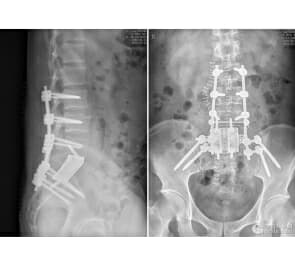

据该调解委员会副主任刘方介绍,北京市卫生局信访案件80%以上为医疗纠纷案件,重复信访、群体信访、非正常上访居高不下。北京市因医疗纠纷到卫生部上访量位列全国第三。刘方称,在医调委受理的纠纷中,出自三级医院的纠纷超过一半,达到57.34%;二级医院占38.83%;一级医疗机构占2.62%;民营医疗机构占1.21%。如果按科室划分,医疗纠纷数量居前十的分别是妇产科、骨科、普外科、急诊科、心外科、心内科、神外、口腔科、呼吸内科和儿科。医生过失主要包括手术或操作损伤周围组织器官,误诊误治,围术期处理不当,漏诊,对医疗意外、并发症处理不当,手术未达到预期效果等。